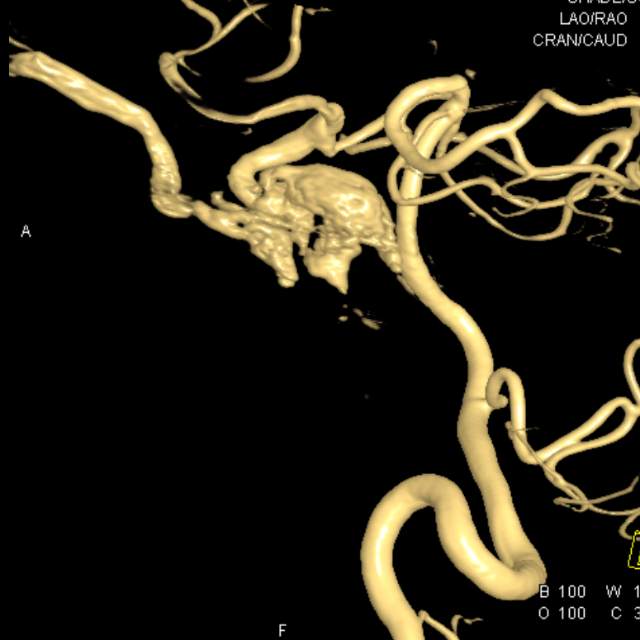

不一样的颈内动脉海绵窦瘘

图片尺寸2000x2667